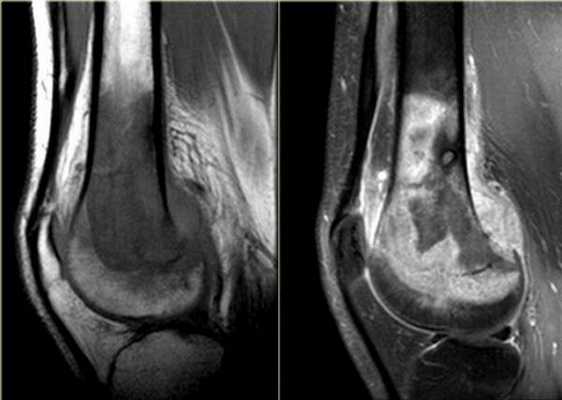

МРТ коленного сустава, разрыв передней крестообразной связки